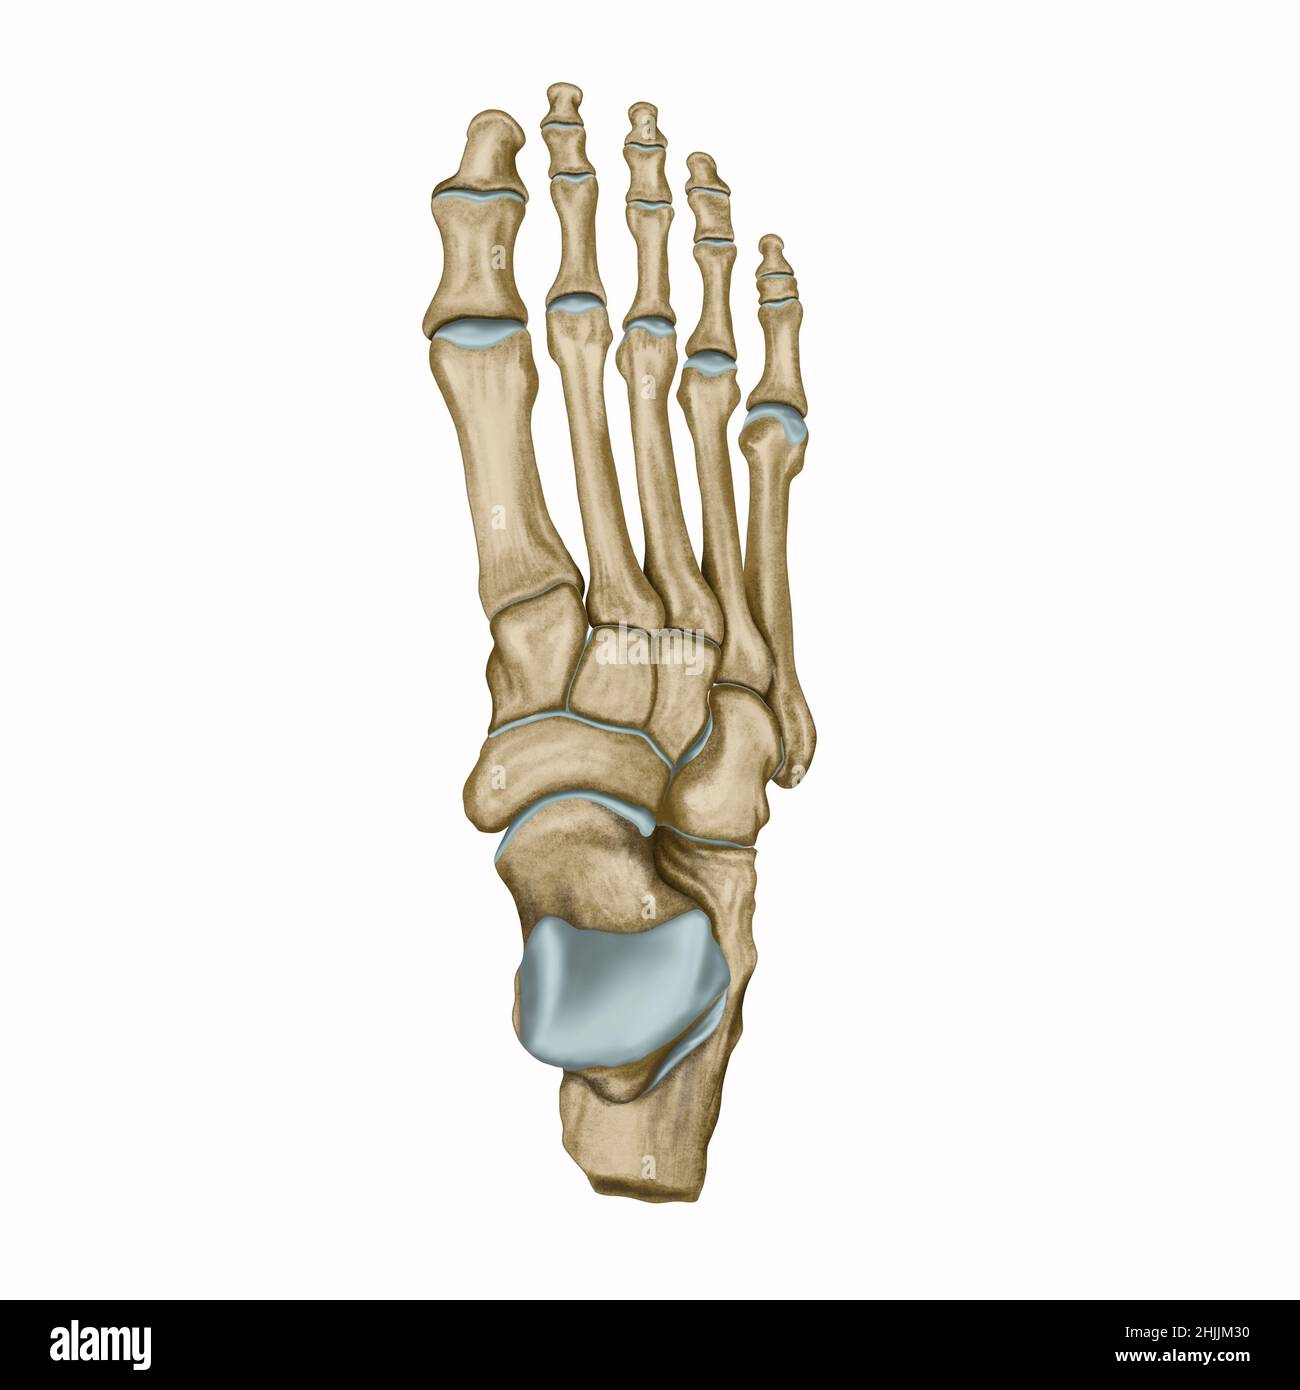

RF2DHMD0H–OS du pied. Anatomie humaine. Le schéma montre l'emplacement et le nom de tous les os du pied.

RF2RYN928–Structure du squelette humain aquarelle. OS du pied. Anatomie et médecine. Illustration orthopédique

RF2HPABHW–OS du pied humain, illustration vectorielle dessinée à la main isolée sur fond blanc, esquisse anatomique en médecine orthopédique

RMK228DY–Partie terminale du membre inférieur, reposant sur le sol au cours de posture droite ; le squelette du pied a 26 os.

RMK227XM–Partie terminale du membre inférieur, reposant sur le sol au cours de posture droite ; le squelette du pied a 26 os.